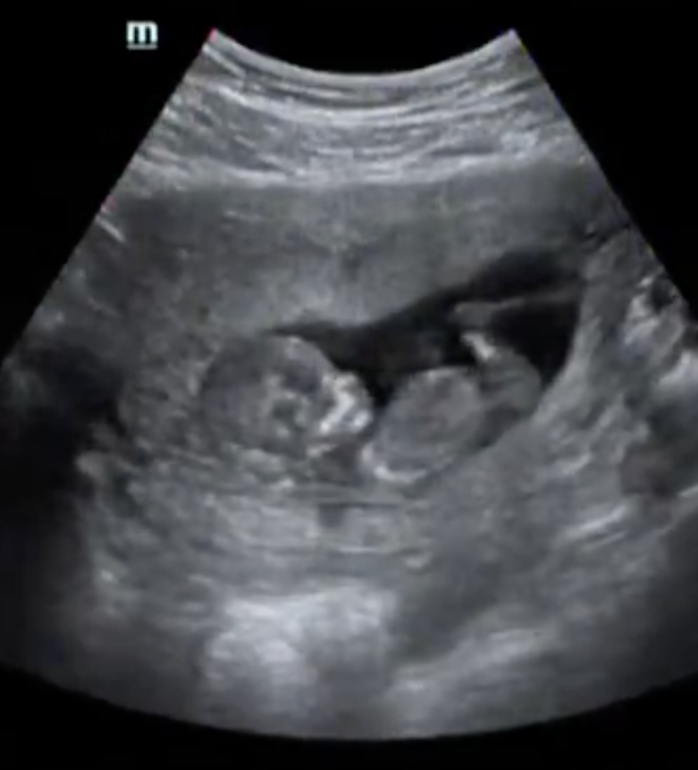

Мы были на первом скрининге, познакомили папу с малышом :) В 12,3 дня КТР был 59,3 мм. Носовая косточка 2,8 мм. ТВП 1,0 мм. Вес 53 гр. Теперь ждем результаты крови (НИПТ), и точно узнаем пол. Врач предположил на 65 процентов девочку (фото бугорочка ниже).

Наш портрет: